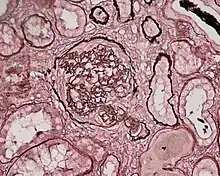

Photomicrograph of a kidney biopsy from a person with crescentic glomerulonephritis showing prominent fibrocellular crescent formation and moderate mesangial proliferation in a glomerulus. Hematoxylin and eosin stain.

Crescentic glomerulonephritis induced by infective endocarditis on PAS staining and immunofluorescence. PAS staining (left) demonstrated circumferential and cellular crescent formation with interstitial nephritis. Immunofluorescence (right) demonstrated C3 positive staining in mesangial area.

Photomicrograph of renal biopsy showing crescent formation and tuft narrowing. Periodic acid silver methenamine stain.

Rapidly progressive glomerulonephritis, also known as crescentic GN, is characterised by a rapid, progressive deterioration in kidney function. People with rapidly progressive glomerulonephritis may present with a nephritic syndrome. In management, steroid therapy is sometimes used, although the prognosis remains poor.[9] Three main subtypes are recognised:[4]:557–558

Histopathologically, the majority of glomeruli present "crescents". Formation of crescents is initiated by passage of fibrin into the Bowman space as a result of increased permeability of glomerular basement membrane. Fibrin stimulates the proliferation of endothelial cells of Bowman capsule, and an influx of monocytes. Rapid growing and fibrosis of crescents compresses the capillary loops and decreases the Bowman space, which leads to kidney failure within weeks or months.